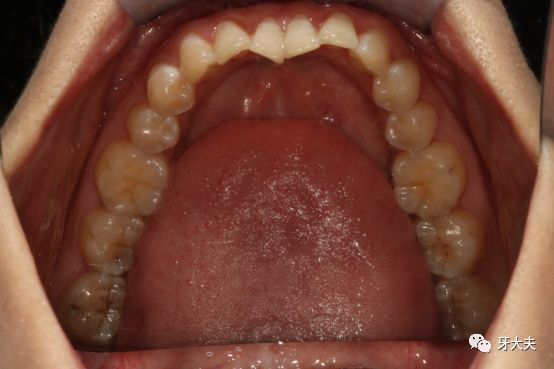

作为一名猪猪女孩,一直被人质疑为什么还要做矫正呢?以前我自己也是这样认为的,从来没想过要整牙,尤其那种钢牙套,还担心牙齿矫正了牙齿会松,牙齿会提前掉,等到自己真正尝试了才发现这些观念都是错的,我做的这一切都是值得的。 先上图。 看牙模更是一目了然这是在牙大夫拍的,是周院长为我看的诊,他说我这属于牙齿不齐,平常自己容易塞牙是有这方面的原因,周院长还和我说,牙齿不齐很容易导致口腔不易清洁,使食物残渣长期滞留,还会容易引起龋齿、牙结石、牙龈炎等,甚至引发牙周病,牙齿松动。